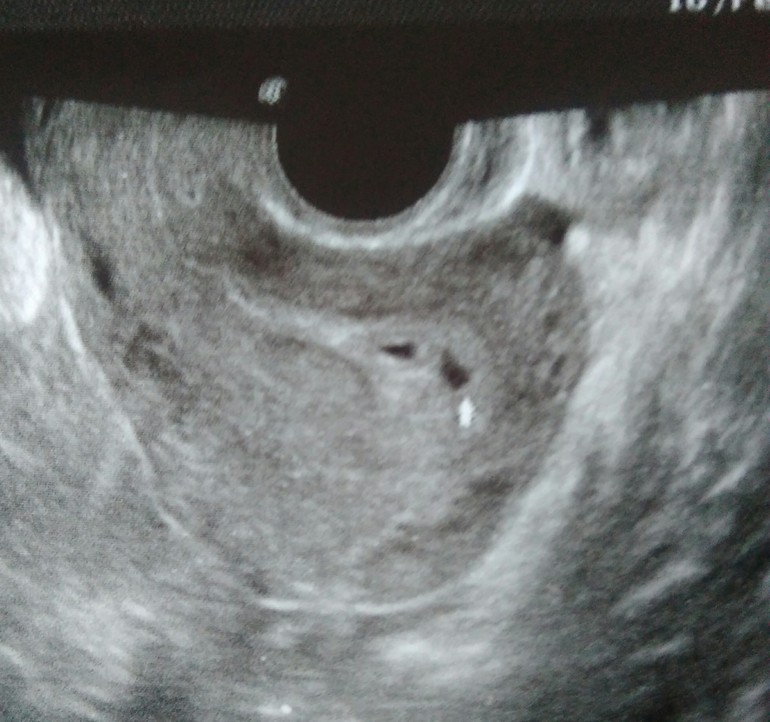

Стрелочкой отмечена гематома ((( Что скажите?

Срок 4 недели. Последние М 13 января. На УЗИ сказали не очень то похоже на 2 пя, больше на 1 пя и гематому( она ее стрелочкой отметила). Плюс ещё и тонус.